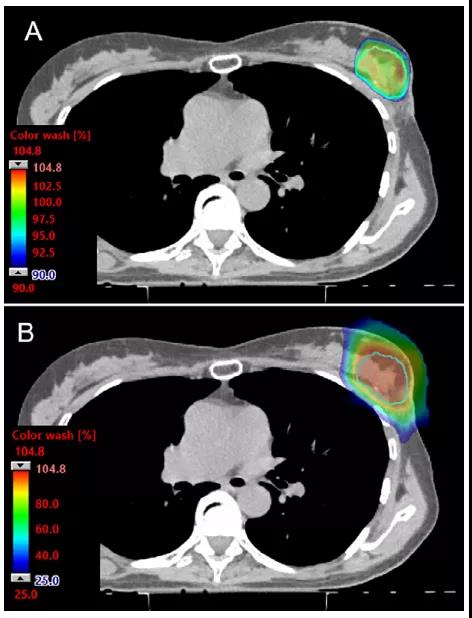

為了避免周圍正常組織的過量劑量,最常用的是正向射野;正向射野可遠端保護心臟和肺及允許呼吸運動方向上的束流路徑。在這種情況下,布拉格峰的遠端劑量衰減被定位在肋骨、肋間隙和IMNs中,可充分利用質子束的遠端劑量急劇衰減優勢。區域淋巴,包括腋窩淋巴結和鎖骨上淋巴結,也可用正向射野治療。對于雙散射質子治療,處理區域的大小通常需要多個匹配射野和匹配線的變化。傳統的皮膚表面匹配線的臨床驗證方法在典型的質子治療遞送系統中存在困難。PBS遞送提供的束斑強度控制可使遞送不需要準直器。PBS射野邊緣設計成緩慢的梯度劑量衰減從而使其對擺位誤差變得不敏感,這對治療大的靶區尤其有利,如雙側乳腺癌(圖2)。此外,PBS整個射野可做到像光子一樣保護皮膚劑量(圖3和圖4)。

圖3. PBS質子治療APBI劑量分布圖。(A)90%的劑量分布顯示了PBS技術實現了高度的劑量適形性和皮膚保護特性。(B)在同一層面下,25%的劑量分布顯示了包括靶區外乳腺組織在內的良好的正常組織保護。